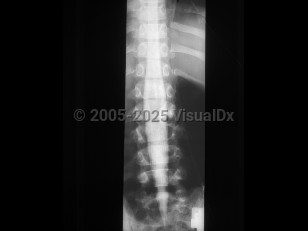

Osteoporotic vertebral compression fracture

Spondylolysis

Spondylolisthesis

Lumbar spinal stenosis

Tuberculous spondylitis

Adult spinal deformity